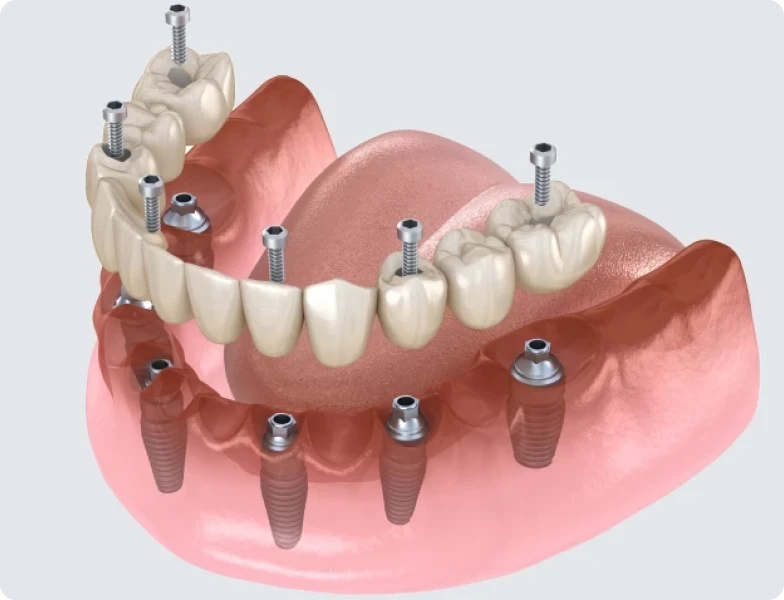

Il existe plusieurs types de prothèses implanto-portées, selon le nombre de dents à remplacer, le nombre d’implants posés et le souhait du patient en matière de confort et de praticité.

Cette solution est vissée ou scellée sur les implants et ne peut pas être retirée par le patient. Elle permet de retrouver une dentition stable, sans mouvement ni inconfort. Elle est utilisée pour remplacer une ou plusieurs dents, voire toute une arcade dentaire.

Dans le cas d’une arcade complète, on parle parfois de « bridge complet sur implants ». Il repose généralement sur quatre à six implants et permet de fixer une prothèse composée de plusieurs dents.

Une fois les implants intégrés, la prothèse peut être réalisée et mise en place. Pour une prothèse fixe, un pilier est vissé sur chaque implant, puis la structure prothétique est fixée. Pour une prothèse amovible, des attaches de rétention sont placées pour permettre l’ancrage.